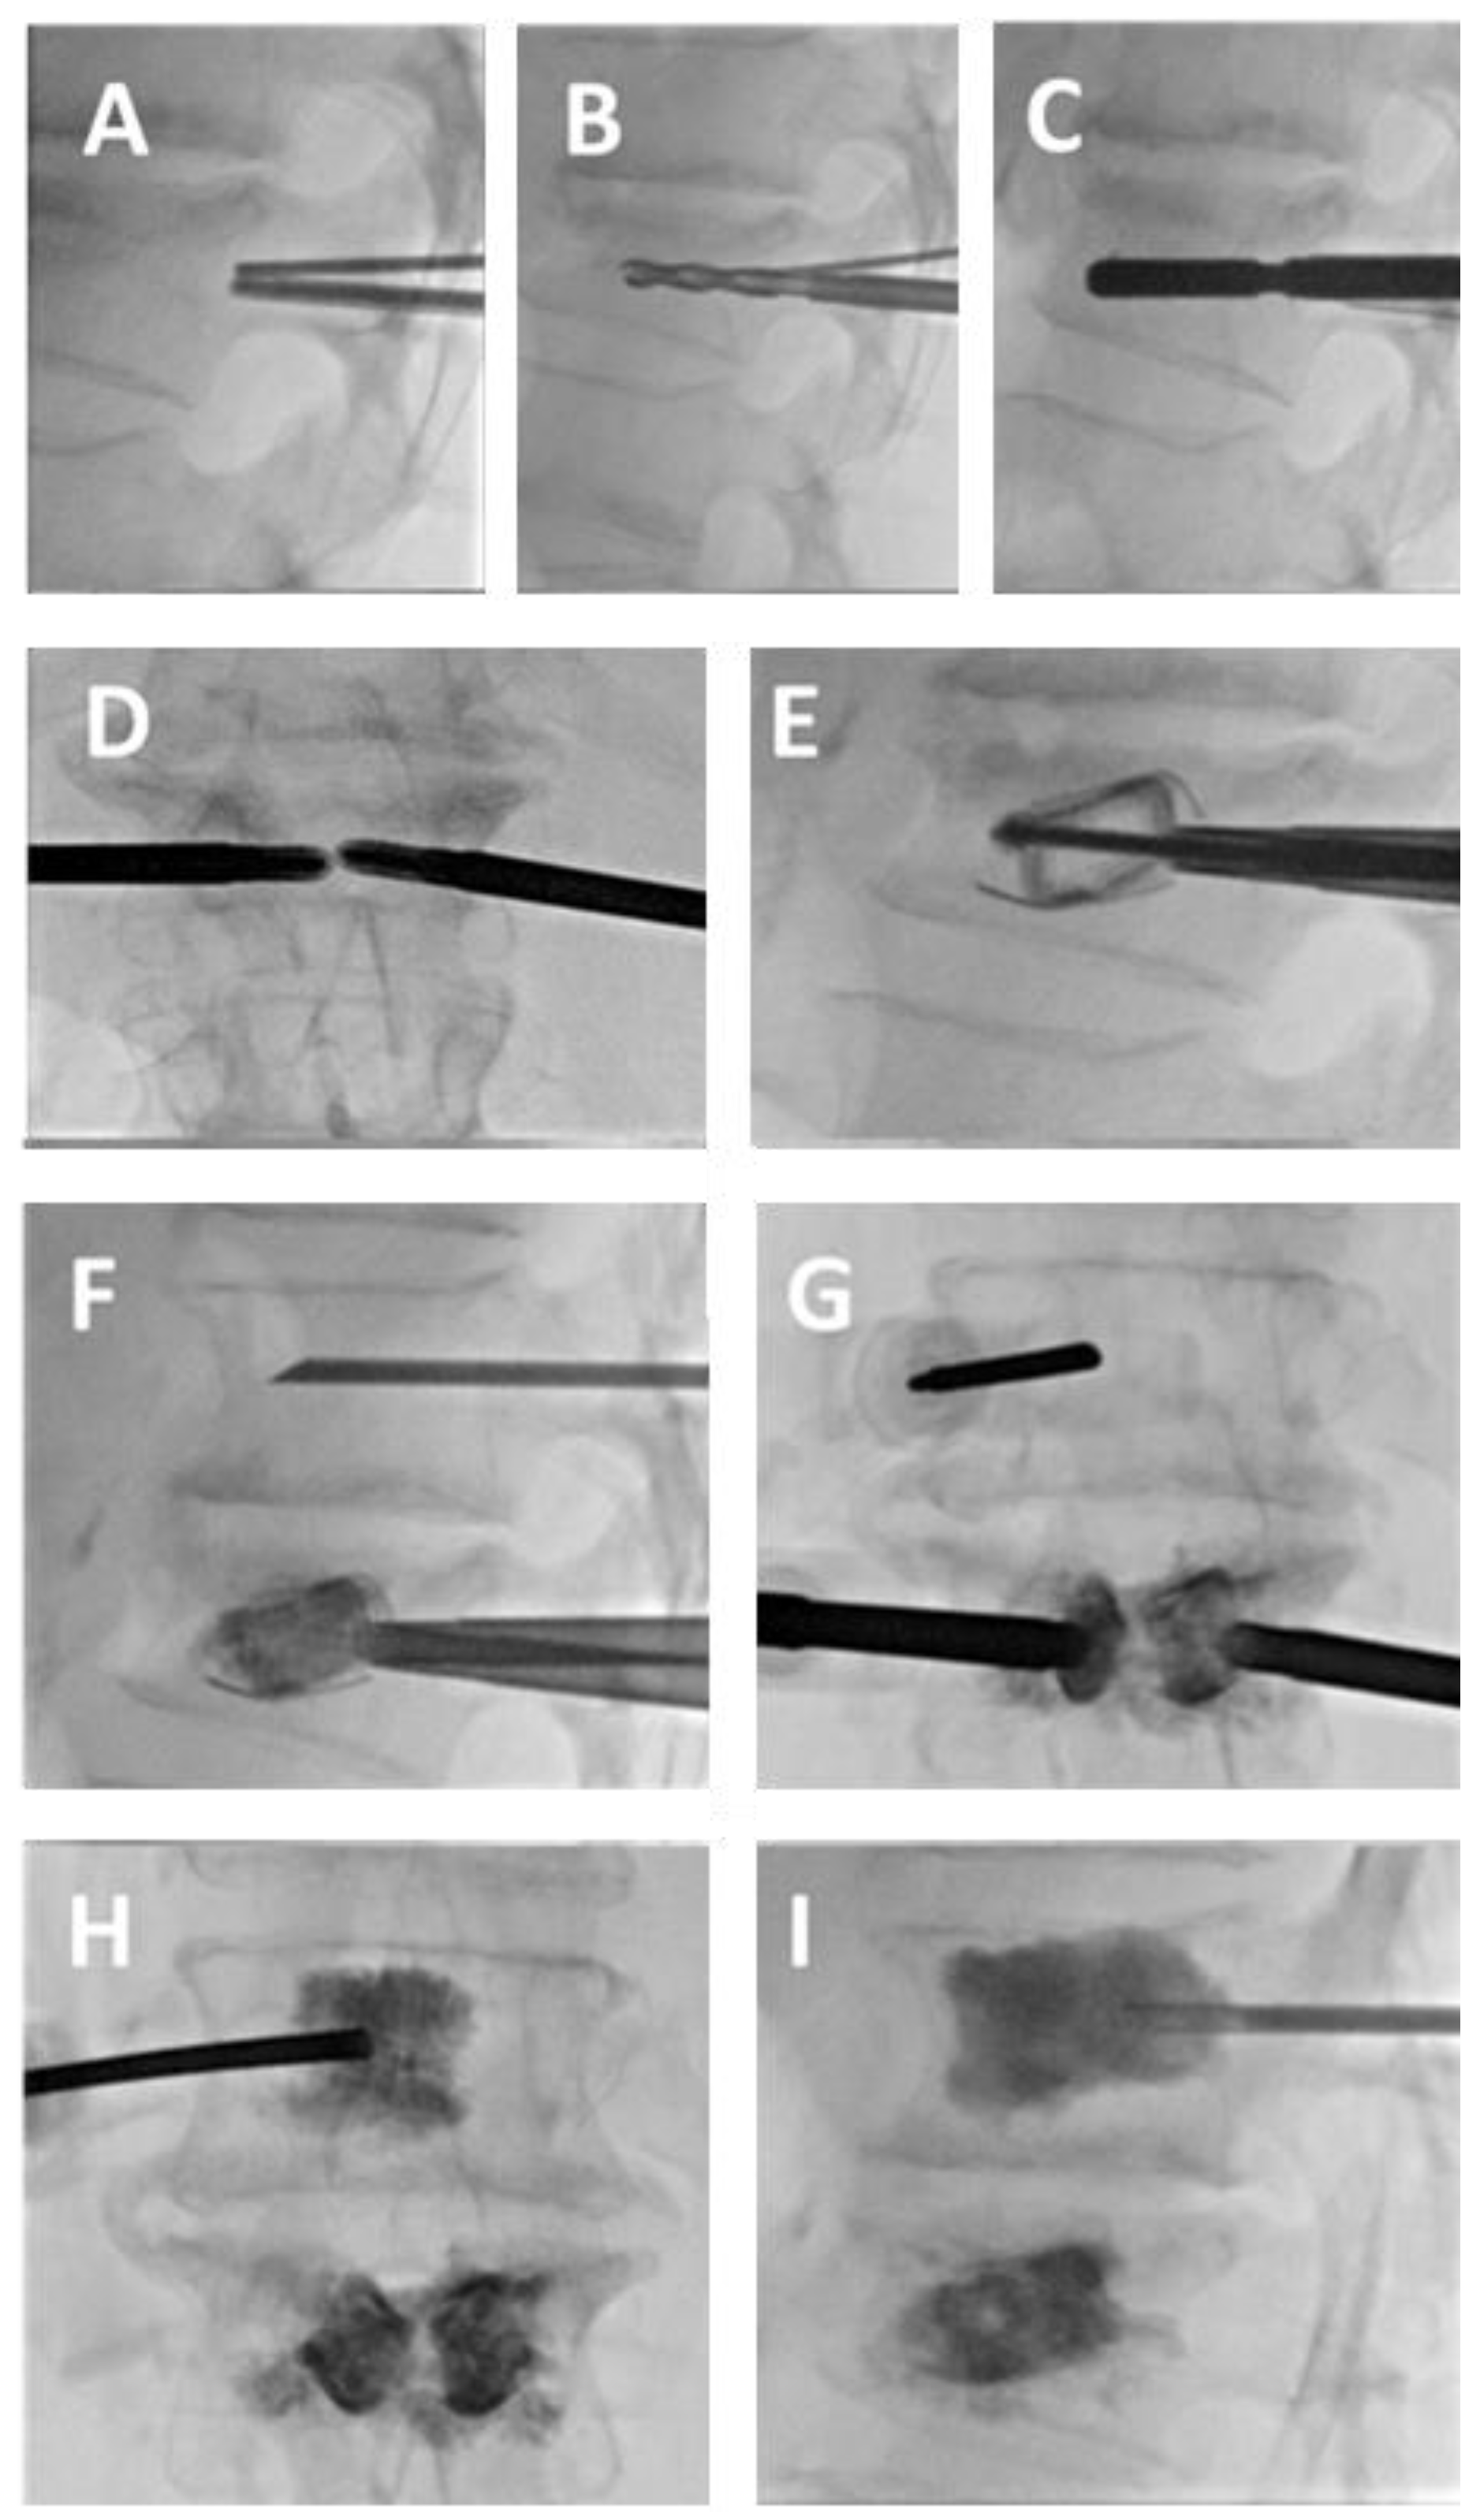

- Pusceddu, C.; Faiella, E.; Derudas, D.; Ballicu, N.; Melis, L.; Zedda, S.; Marsico, S. Re-expansion of vertebral compression fractures in patients with multiple myeloma with percutaneous vertebroplasty using spinejack implants: A preliminary and retrospective study. Front. Surg. 2023, 10, 1121981. [Google Scholar] [CrossRef]

- Pusceddu, C.; Marsico, S.; Derudas, D.; Ballicu, N.; Melis, L.; Zedda, S.; de Felice, C.; Calabrese, A.; De Francesco, D.; Venturini, M.; et al. Percutaneous Vertebral Reconstruction (PVR) Technique of Pathological Compression Fractures: An Innovative Combined Treatment of Microwave Ablation, Bilateral Expandable Titanium SpineJack Implants Followed by Vertebroplasty. J. Clin. Med. 2023, 12, 4178. [Google Scholar] [CrossRef]